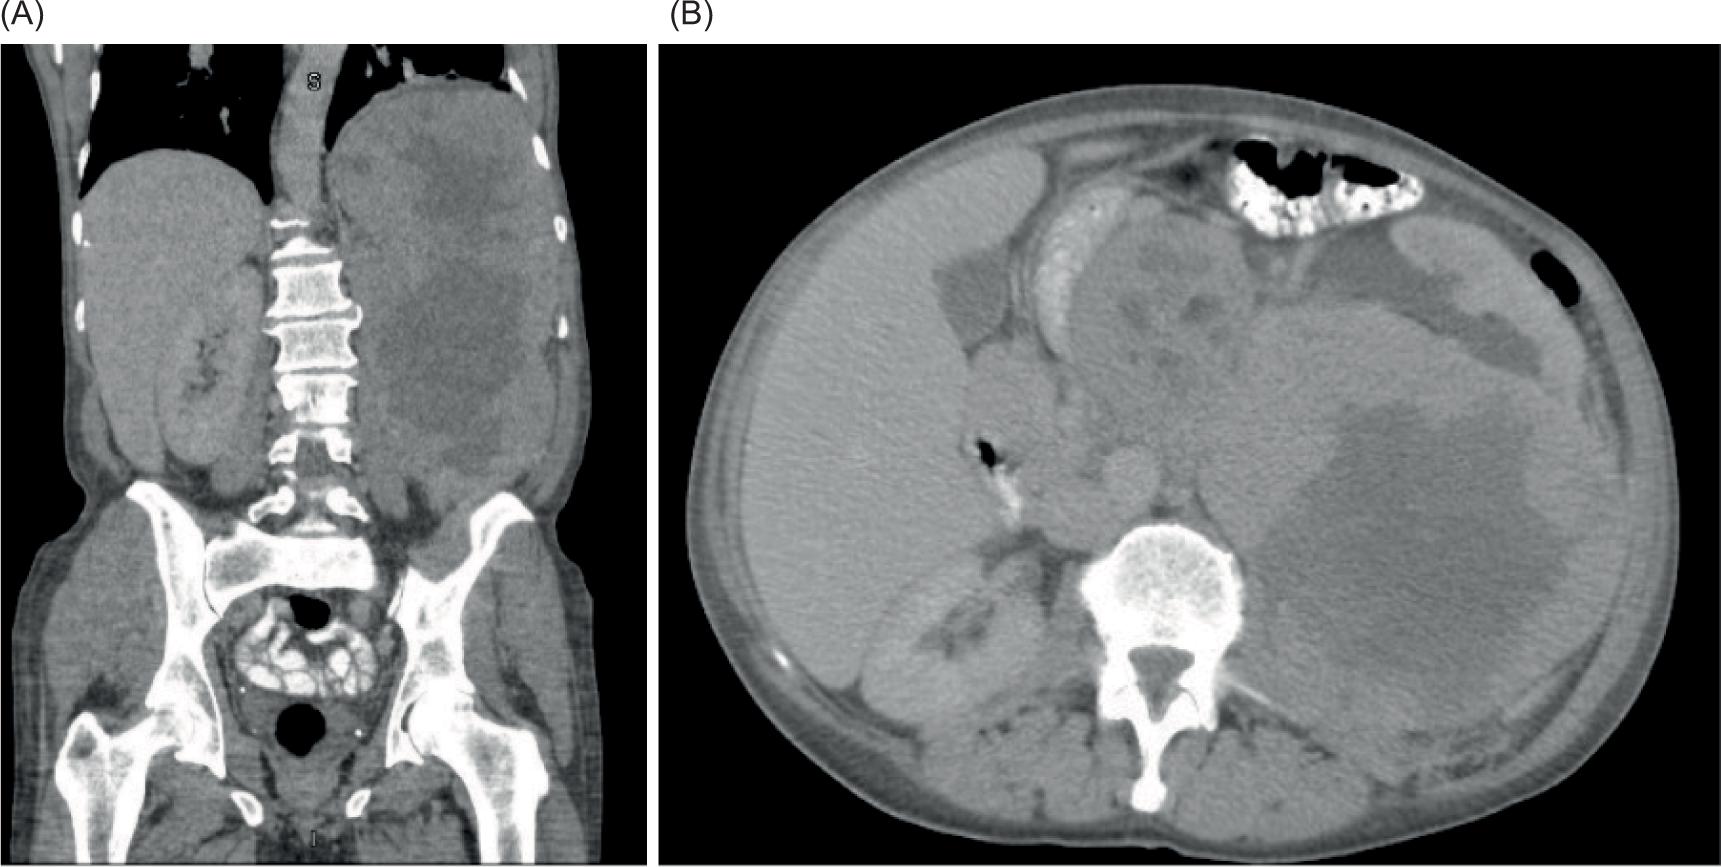

At 4 months follow-up from the VATS, a restaging CT scan demonstrated an enlarged liver with numerous low-density masses within the liver, including a conglomerate of masses within the right lobe of the liver, and an increase in the size and number of pulmonary nodules (Figure 4). The restaging CT also demonstrated the development of ascites in the pelvis and a probable tumor implant in the left peritoneal cavity, lateral to the psoas muscle. The patient was started on systemic temsirolimus, an mTOR inhibitor. Initially, after 3 months on temsirolimus, the patient demonstrated a dramatic improvement both clinically and radiographically. However, he ultimately stopped responding to temsirolimus. He was then transitioned to gemcitabine but unfortunately, the patient eventually passed away after this treatment alteration.

Figure 4: Abdominal CT image. CT image demonstrating massive tumor recurrence in the liver after surgical resection of primary tumor and prior to initiation of temsirolimus.